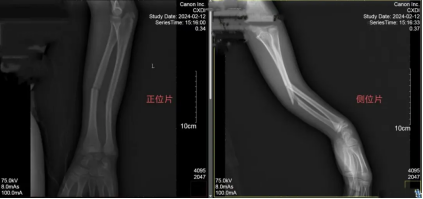

李某立即打电话联系了家属,家人把他送到我院骨伤二科就诊,经检查发现,李某左臂尺桡骨骨干双骨折。

李某检查显示左臂尺桡骨骨干双骨折